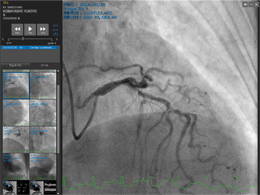

- 高速な動画再生

- デュアルモニター対応

自社開発のアルゴリズムにより、高速(1秒以内)で再生されます。

検査画像の中からペアになる画像を自動検出し、2分割表示します。